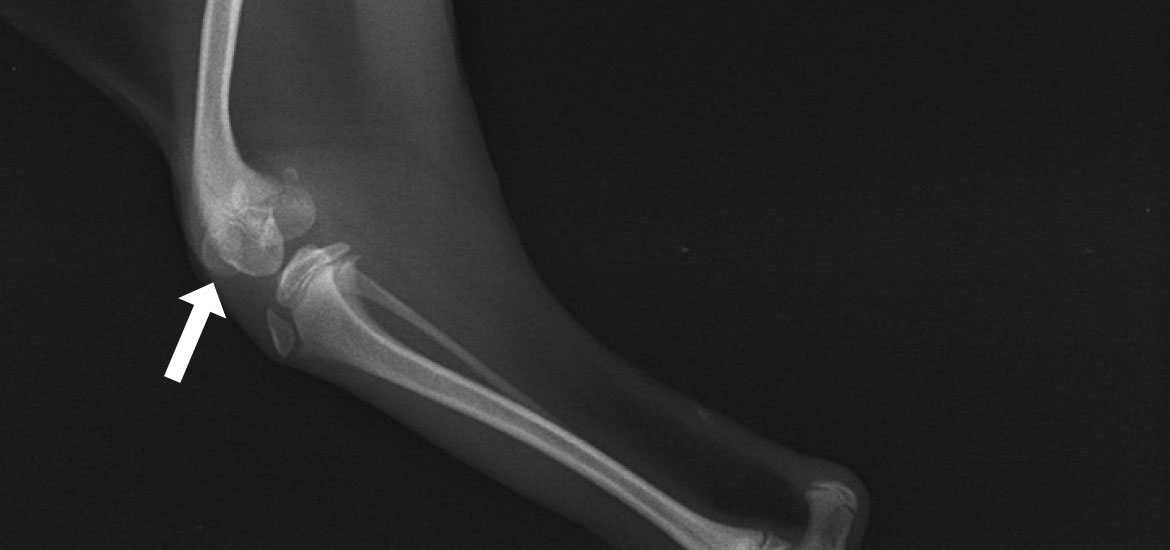

脛骨粗面転位術

けいこつそめんてんいじゅつ

膝関節のパーツが本来の配置・配列になるよう縦軸を矯正。

成長期に脱臼が起きると、膝蓋骨と膝蓋靱帯に引っ張られる形で脛骨もねじれます。その状態で成長すると、脛骨粗面(膝蓋靭帯が付着しているザラザラした部分)がまっすぐ前を向かず、内向きまたは外向きで定着してしまいます。滑車造溝術で溝を造り、脱臼を整復しても、脛骨のねじれをそのままにしておくと、脛骨粗面に付着している膝蓋靭帯が膝蓋骨を引っ張り戻すことになり、再脱臼のリスクが高くなります。

脛骨粗面転移術とは、粗面を膝蓋靭帯が付着したままの状態で骨切りし、大腿骨の溝、膝蓋骨、脛骨粗面が本来の縦一直線で並ぶ正しい位置まで移動させ、ピンで固定させる手術です。膝蓋骨脱臼において、滑車造溝術と組み合わせて施されることの多い術式になります。